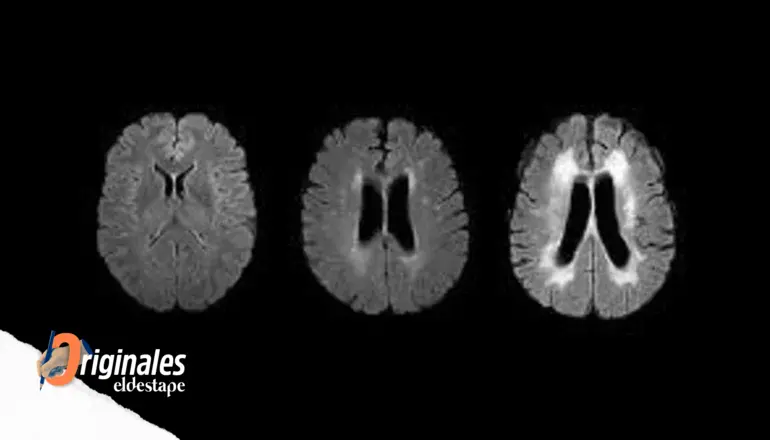

No es necesario ser un científico avezado para advertir que nuestro cerebro se desarrolla y envejece condicionado tanto por su bagaje genético como por el ambiente al que se expone. Y mientras algunos se mantienen jóvenes y vitales hasta edades muy avanzadas, otros decaen antes. Otra forma de interpretarlo sería que la “edad cerebral” de estos últimos es mayor que la que le correspondería de acuerdo con el calendario. Algunos de los factores que influyen en su “envejecimiento”, como la interacción social, la demanda cognitiva y ciertas patologías, se conocen bien. Pero un trabajo que acaba de publicarse en la revista Nature Medicine aplicando técnicas de inteligencia artificial (“aprendizaje profundo” o deep learning) en grandes bases de datos de resonancia magnética y electroencefalogramas (EEG) intenta ofrecer más precisiones (Brain clocks capture diversity and disparities in aging and dementia across geographically diverse populations). De acuerdo con esta investigación, que firma una colaboración internacional de 70 autores, otros como la contaminación y las desigualdades económicas o de acceso a la salud influyen en el “tic tac” de nuestro “reloj cerebral”; especialmente en el envejecimiento y la demencia.

Para llegar a estas conclusiones, alimentaron con neuroimágenes de esas personas los modelos de IA que “aprenden” de las interacciones [cerebrales] de alto orden, algoritmos que computan un número altísimo de las mismas. “Lo primero que logramos es un sistema que predice la edad cronológica con bastante precisión –afirma Ibáñez–. Después, estimamos la diferencia entre la edad cronológica y la edad esperada del cerebro de acuerdo con el modelo previo. Así podemos medir la brecha (gap, en inglés), que puede ser de aceleramiento (cuando el cerebro está más viejo de lo que correspondería a su edad, su “tic tac” es más rápido) o de retraso, cuando el cerebro está más joven de lo esperado”. El rango promedio de aceleramiento del reloj cerebral en América latina fue de cinco años.

¿Cómo calculan la edad cerebral? “Uno provee al modelo con imágenes de entrenamiento, en particular de cómo está conectado el cerebro –explica Moguilner–. Usamos unas técnicas que se llaman de ‘conectividad funcional’, tanto en resonancia magnética como en EEG. La máquina va aprendiendo qué patrón de conectividad corresponde a qué edad. Luego, le damos un nuevo patrón de conectividad, pero no le decimos a la computadora que edad tiene, tiene que predecirla. Y lo que vimos fue que las predicciones indicaban una edad mayor cuando estos sujetos eran de países con mayor disparidad”.

Éste no es un estudio poblacional, sino probabilístico. Sin embargo, los científicos lo consideran sólido porque analizaron datos de dos tipos de técnicas (resonancia magnética funcional y electroencefalografía) y ambas arrojaron los mismos resultados. “Tenemos una doble validación cruzada: entrenamos un modelo y testeamos con datos totalmente diferentes, y los dos nos dan lo mismo”, aclara Ibáñez.